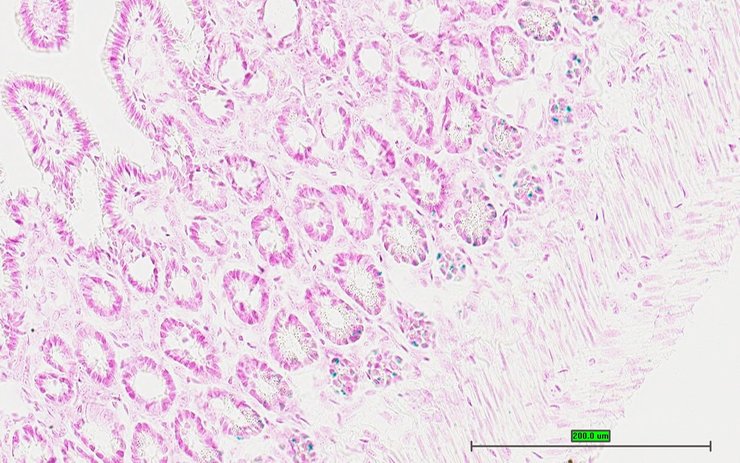

TS28: ileum Present UC Davis_1877361

TS28: colon Present UC Davis_1877362